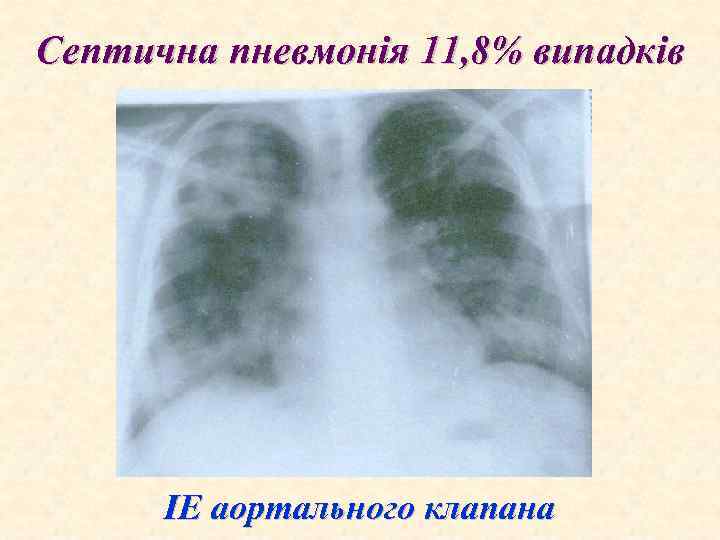

Септична пневмонія 11, 8% випадків ІЕ аортального клапана

ЕНДОКАРДИТИ Додаткові методи діагностики ІЕ. 1. Посів крові: слід провести за 24 години до початку антибактеріальної терапії, посів проводиться 3 рази з інтервалом годину з 2 -3 1 різних вен 2 Ехокардіографія: вегетацій на клапанах, ендотелії аорти, хордах, папілярних м'язах 3. Гематологічні прояви: а) нормохромна анемія; b) збільшена швидкість осідання еритроцитів; с) лейкоцитоз; d) тромбоцитопенія; е) підвищений сироватковий -глобулін. 4. Аналіз сечі: в нормі або ж є гематурія, протеїнурія, еритроцитарні циліндри. 5. Електрокардіографія: дає можливість з'ясувати стан коронарного кровоплину, наявність пошкоджень провідної системи тощо. 6. Рентгенографія грудної клітки: конфігурацій (аортальна, мітральна, куляста), легеневого застою, пневмоній, інфарктів та абсцесів легень.